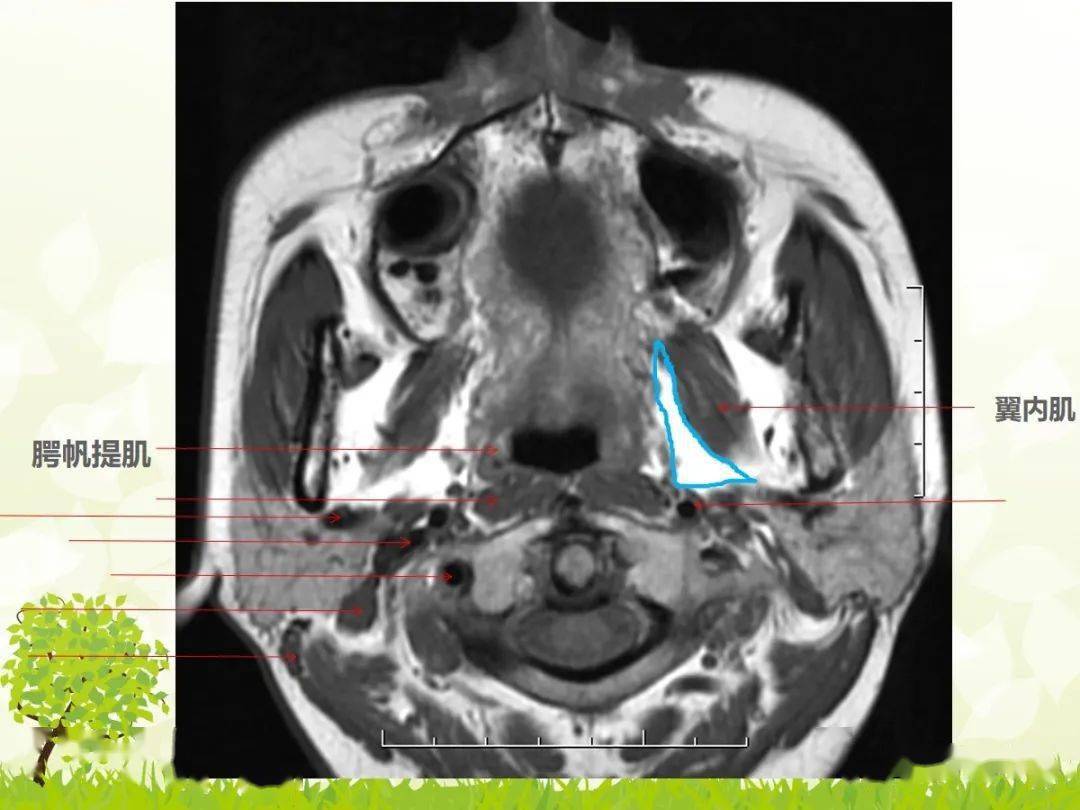

咽旁间隙解剖及常见病变影像表现

图片尺寸1080x810